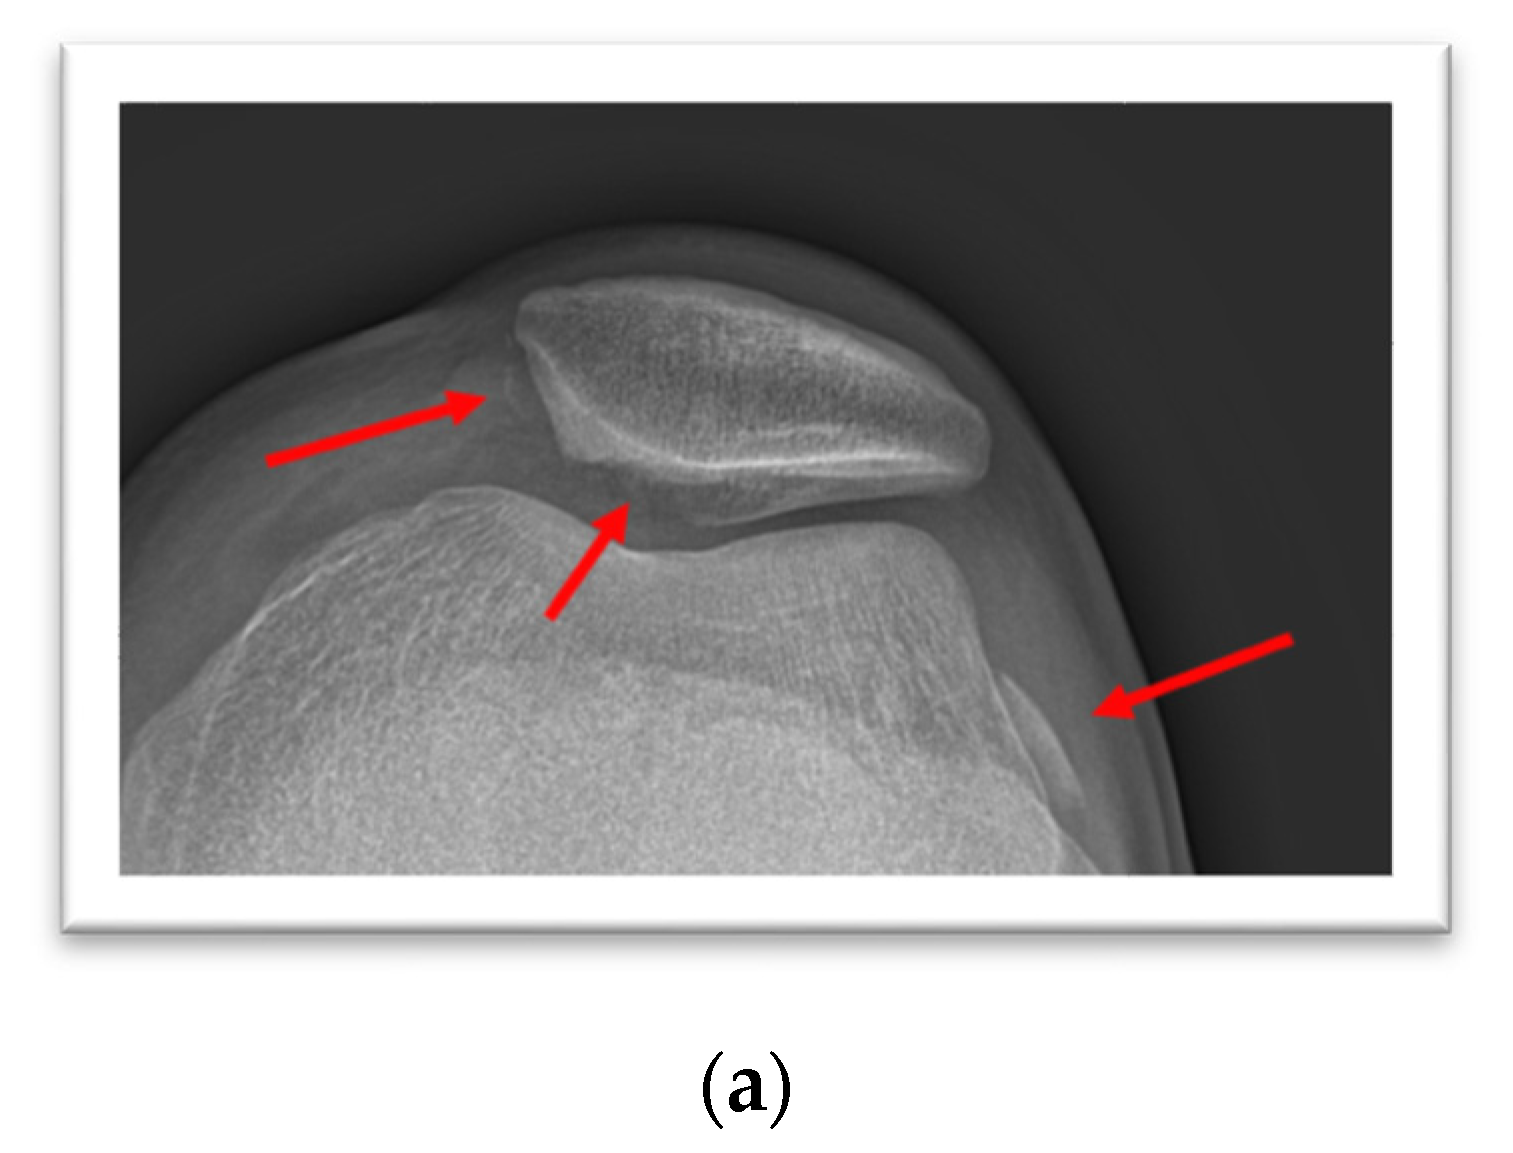

3. Case Presentation

4. Case Presentation

5. Case Presentation